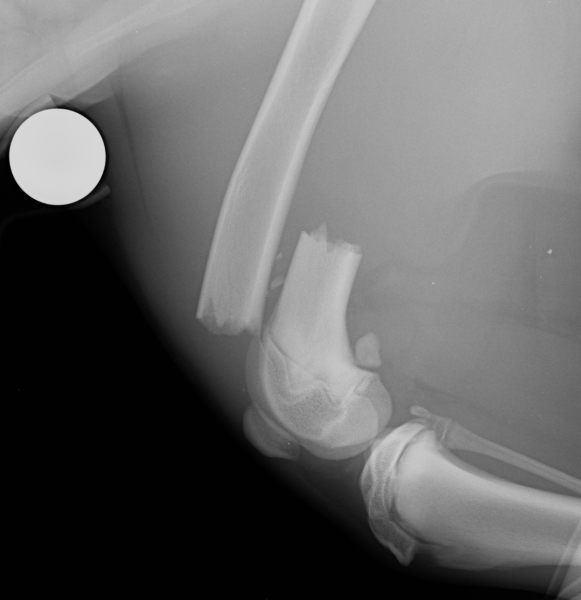

- The decision-making process and surgical treatment of common fractures, including humeral condylar fractures, radius/ulna fractures, pelvic fractures, femoral fractures, tibial fractures, physeal fractures